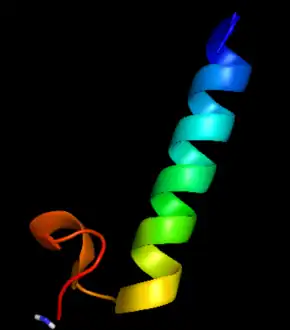

| Figure 1: Immature Calcitonin | |

A 3D cartoon of procalcitonin's daughter compound, calcitonin |

PCT is a member of the calcitonin (CT) superfamily of peptides. It is a peptide of 116 amino acids with an approximate molecular weight of 14.5 kDa, and its structure can be divided into three sections (see Figure 1):[9] amino terminus (represented by the ball and stick model in Figure 1), immature calcitonin (shown in Figure 1 from PDB as the crystal structure of procalcitonin is not yet available), and calcitonin carboxyl-terminus peptide 1.[9] Under normal physiological conditions, active CT is produced and secreted in the C-cells of the thyroid gland after proteolytic cleavage of PCT, meaning, in a healthy individual, that PCT levels in circulation are very low (<.05 ng/mL). The pathway for production of PCT under normal and inflammatory conditions are shown in Figure 2.[10] During inflammation, LPS, microbial toxin, and inflammatory mediators, such as IL-6 or TNF-α, induce the CALC-1 gene in adipocytes, but PCT never gets cleaved to produce CT.[10] In a healthy individual, PCT in endocrine cells is produced by CALC-1 by elevated calcium levels, glucocorticoids, CGRP, glucagon, or gastrin, and is cleaved to form CT, which is released to the blood.[10]